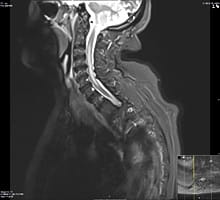

An MRI image showing areas of inflammation and scarring in the brain of an MS patient

An MRI image showing areas of inflammation and scarring in the brain of an MS patient.

Multiple sclerosis or MS is an immune-mediated disorder in which the patients’ own immune system attacks their brain and/or their spinal cord causing inflammation and scarring. It commonly manifests in the form of relapses and remissions but some forms of the disease are progressive. It can cause variable neurological manifestations and it usually affects young adults. Early and prompt treatment can prevent relapses and slow down or prevent disability. Learn more about multiple sclerosis.